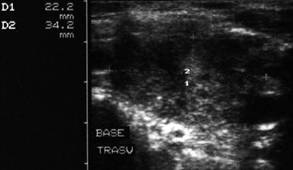

Lob drept , proiectie trasversala si longitudinala.

Femeie 19 ani. Leziune marcant hipoecogen cu intarire posterioara, de 16x20x26mm (4 cc) in lobul drept.

Examen citologic: macrofagi, fara tireocite.

Femeie 17 ani. Voluminoasa tumefactie (32x40x45mm, 29 cc) in lobul stang, intens hipoecogena, cu echo densitati in interior, intarire posterioara. Deviatia tracheei spre dreapta.

Examen citologic; chist coloid